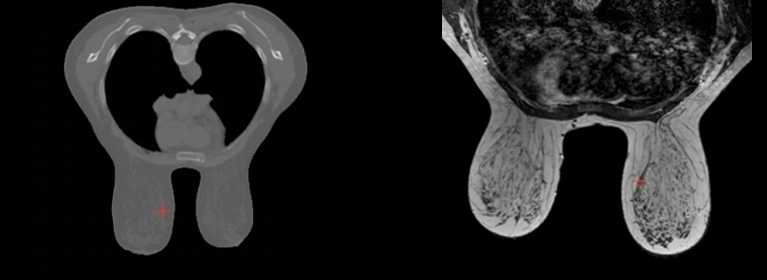

En esta línea tienen una especial relevancia las aplicaciones al ámbito de la biomecánica (simulaciones de estructuras óseas incluyendo remodelación, conjuntos hueso-implante y tejidos blandos como mama, cornea, hígado, aorta, ...) para planificación quirúrgica y cirugía asistida por ordenador. Se realizan también simulaciones de tribocorrosión en materiales usados en aleaciones biomédicas, cuyos resultados numéricos se contrastan con ensayos experimentales. Para las simulaciones, el grupo dispone de tecnología propia que permite crear avatares numéricos patient-specific directamente a partir de imágenes médicas. Esta tecnología puede ser utilizadas también para, mediante meros ensayos numéricos, la caracterización de propiedades de materiales cuya estructura esté representada por imágenes 3D.

Finalmente, el grupo trabaja también en la combinación de tecnologías clásicas de mecánica computacional con tecnologías Machine Learning que, por su versatilidad, nos han permitido desarrollar aplicaciones orientadas a la optimización de componentes estructurales, la segmentación de tejidos biológicos, el diagnóstico de patologías, la caracterización de propiedades de materiales, etc